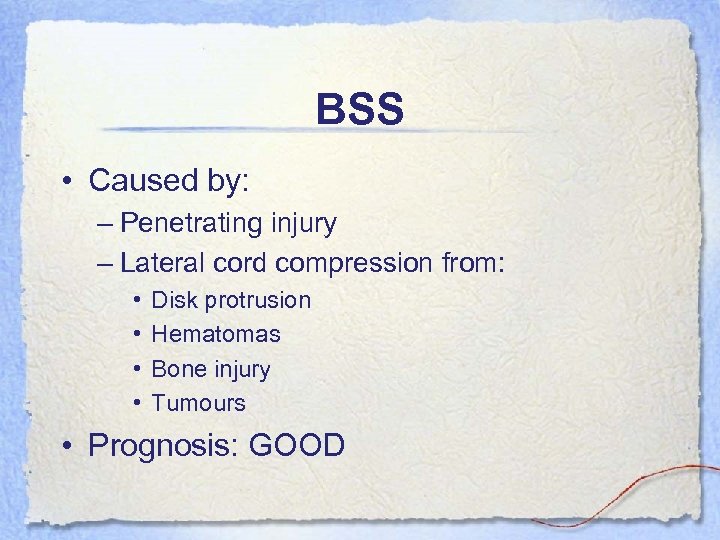

BSS • Caused by: – Penetrating injury – Lateral cord compression from: • • Disk protrusion Hematomas Bone injury Tumours • Prognosis: GOOD

BSS • Caused by: – Penetrating injury – Lateral cord compression from: • • Disk protrusion Hematomas Bone injury Tumours • Prognosis: GOOD